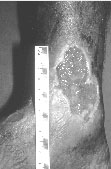

The blood supply of the leg consists of blood vessels called veins that return blood from the lower legs to the heart, assisted by valves that ensure that the “one-way” upward flow of blood. In many patients with venous leg ulcers, these valves are not working properly, causing blood to “pool” in the lower legs. This can lead to swelling and darkening of the skin, and eventually to venous leg ulcers (Figure 4).

Fig 4 Venous Leg Ulcer - The skin of the leg can turn dark brown or red.

The ulcer is usually wet and weepy, with heavy discharge.